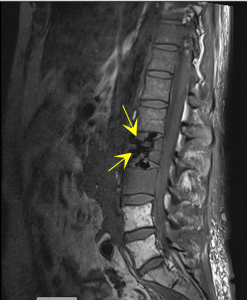

After clinical evaluation, vertebral compression fractures are diagnosed using imaging studies such as:

-

X-ray

CT scan

MRI

Bone scintigraphy

These tests also help determine whether the fracture is recent or old, which is crucial for selecting the appropriate treatment.